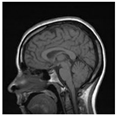

Table 1 shows the original image, marked image, encrypted image, the decrypted image, and the correlation between extracted blocks and original blocks after decryption using the Double Random Phase Encryption. It is clear that the encryption increases the security, and the mean correlation between the recovered mark and the original mark is measured to be 0.9 in both cases.

The PSNR and SSIM between the original image and marked image are 35.99 db and 0.97, respectively, which means that the marking does not affect the quality of the original image and keeps the invisibility of mark in the image. After encrypting the marked image using the DPRE algorithm, the results show that PSNR and SSIM between the encrypted and marked image are 12 db and 0.1, which verifies the strength of the suggested cryptosystem, as there is no similarity between them. Moreover, the results show that the correlation between the embedded rows and columns with the original is near to 1, verifying the robustness of the mark or signature.

The study of the effect of noise on the encrypted and marked image in addition to the effect of noise on the recovered mark is shown in Table 2. It is clear that by increasing the additive white Gaussian noise (AWGN), the SNR between the noisy image and original image takes values from 5 dB to 50 dB, the correlation between the original and recovered rows and column with original, i.e., the correlation between extracted blocks and original blocks increased from 0.1 to 0.75, which verifies that the recovered mark does not match the original mark. The correlation values which are used to express the similarity between blocks in a marked image and blocks in a non-marked image are calculated in Table 3. A higher correlation means that the image is marked, this is explained as the blocks which have a mark within row or columns get a high value of correlation, which is near 1, but the others with no mark get low values of correlation. Correlation values in Figure 4 ensure the possibility of mark verification, which means that we can verify the presence of a mark when the correlation between the recovered rows and columns and the original is equal to 1, as it illustrates the correlation between blocks of a marked image which equals to 1. As a result, this confirms that the image is marked. In Table 3, we did not apply marking to the image, and we divided the image by the same technique and compared the blocks with each other. We find that the correlation is close to zero and this means that the image is not marked by this method. As a result, we verify the originality of the image which contains the mark.

From Table 4, it has been noticed that the correlation of the original image is high (CF = 0.9143) and close to one. In contrast, the correlation of the encrypted image is minimal (CF = 0.0071) and close to zero, which demonstrates that encryption using the DRPE algorithm can break the relativity efficiently, possesses a robust capability to withstand a statistical attack, and does not alter the quality of the output decrypted image after inserting the mark, i.e., the decrypted image is the same as the original.